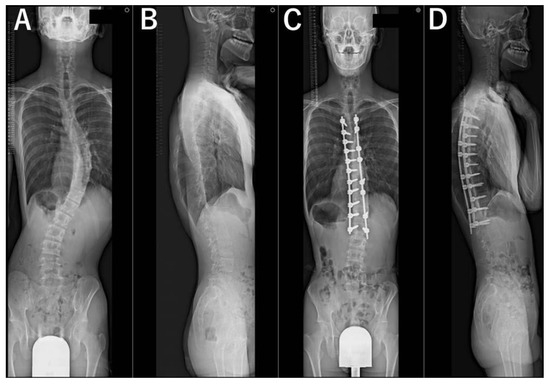

2. Materials and Methods

3. Results

3.3. Radiographic Evaluations